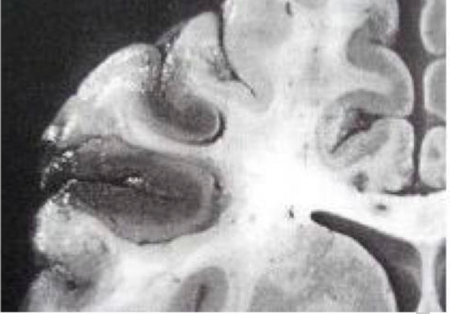

Etiologi kelainan manakah yang paling mirip dengan yang ditunjukkan di bawah ini?

A. Naiknya tekanan intracranial

B. Penyakit Aterosklerotik

C. Infeksi SSP

D. Gangguan Neurodegeneratif

E. A, B, C dan D semuanya salah

A